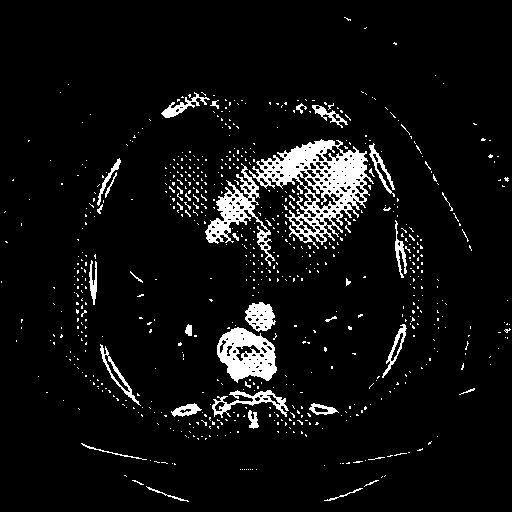

Generated VENOUS CT scan (A→B translation)

Full window (WL 1023.5, WW 4095 β†’ Low βˆ’1024, High +3071)

Actual HU range: [-1024.0, 3071.0]